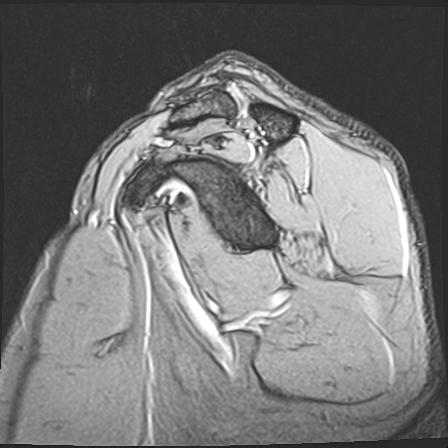

60058 3/9 11/4 右肩 2R+MRI 73歳男性 肩腱板損傷